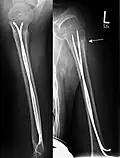

Elastisch stabile intramedulläre Nagelung (ESIN)

Es handelt sich bei den Implantaten um biegsame elastische Nägel aus Edelstahl oder Titan, die an ihrer Spitze eine Abflachung und eine Abwinkelung tragen, um in der Markhöhle von Röhrenknochen zu gleiten und sich durch die elastische Spannung in der Markhöhle zu verklemmen. Bei geeigneten Brüchen aller großen Röhrenknochen (Oberschenkel, Schienbein, Oberarm, Speiche und Elle) wird durch einen kleinen Hautschnitt in Nähe aber unter Schonung der Wachstumsfuge die Markhöhle des Knochens mit einer Ahle eröffnet. Durch diese Öffnung wird in absteigender oder aufsteigender Richtung ein erster elastischer Nagel eingeführt. Er wird mit drehenden Bewegungen über die Bruchregion geschoben, die unter Röntgensicht korrekt geschlossen oder bei Nicht-Reponierbarkeit offen durch einen Schnitt eingerichtet wird. Die aufgebogene Spitze kann auch als Hilfe bei der Einrichtung (Repositionshilfe) genutzt werden. Unter weiterem Vorschieben verankert sich der Nagel endgültig kurz unterhalb der jeweiligen anderen Wachstumsfuge des Röhrenknochens. Zur ausreichenden Stabilisierung wird mit Ausnahme bei den paarigen Unterarmknochen ein zweiter (oder selten auch ein dritter) Nagel durch einen separaten Zugang in gleicher Verlaufsrichtung eingeführt.

Wenn beide Nägel eingeschlagen sind, werden sie mit einem Bolzenschneider gekürzt, so dass sie unter der Haut verschwinden, aber noch ausreichend lang aus dem Knochen stehen, damit sie wieder zu entfernen sind. Meist wird die Versorgung von beiden Seiten einer Extremität (innen und außen) durchgeführt, es können aber auch beide Nägel z. B. am Oberarm von seitlich absteigend eingeführt werden, wenn auf der Innenseite Gefäße oder Nerven durch die Implantation gefährdet wären. Die ESIN erreicht bei Kindern und Jugendlichen bei geeigneten Brüchen eine gute Übungsstabilität und früh eine Belastungsstabilität. Eine zusätzliche Gipsbehandlung ist nicht notwendig. Die Nägel können durch einen ebenso kleinen Hautschnitt nach wenigen Monaten wieder entfernt werden.

- Fallbeispiele

-

Mit ESIN versorgter schultergelenknaher Oberarmbruch beim Kind. Ausheilungsbild mit deutlich sichtbarem Frakturkallus (Pfeil) -

Komplette Unterarmschaft-fraktur beim Kind mit deutlicher Knickbildung -

Versorgung derselben Fraktur mit je einem Prevot-Nagel (ESIN) in Radius und Ulna